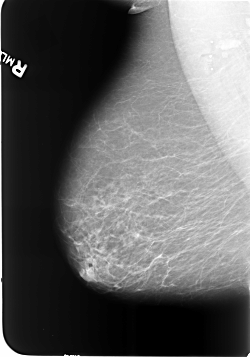

B_3473_1.RIGHT_CC

RIGHT_CC LINES 5736 PIXELS_PER_LINE 3688 BITS_PER_PIXEL 12 RESOLUTION 50 NON_OVERLAY

RIGHT_MLO LINES 5712 PIXELS_PER_LINE 3992 BITS_PER_PIXEL 12 RESOLUTION 50 NON_OVERLAY